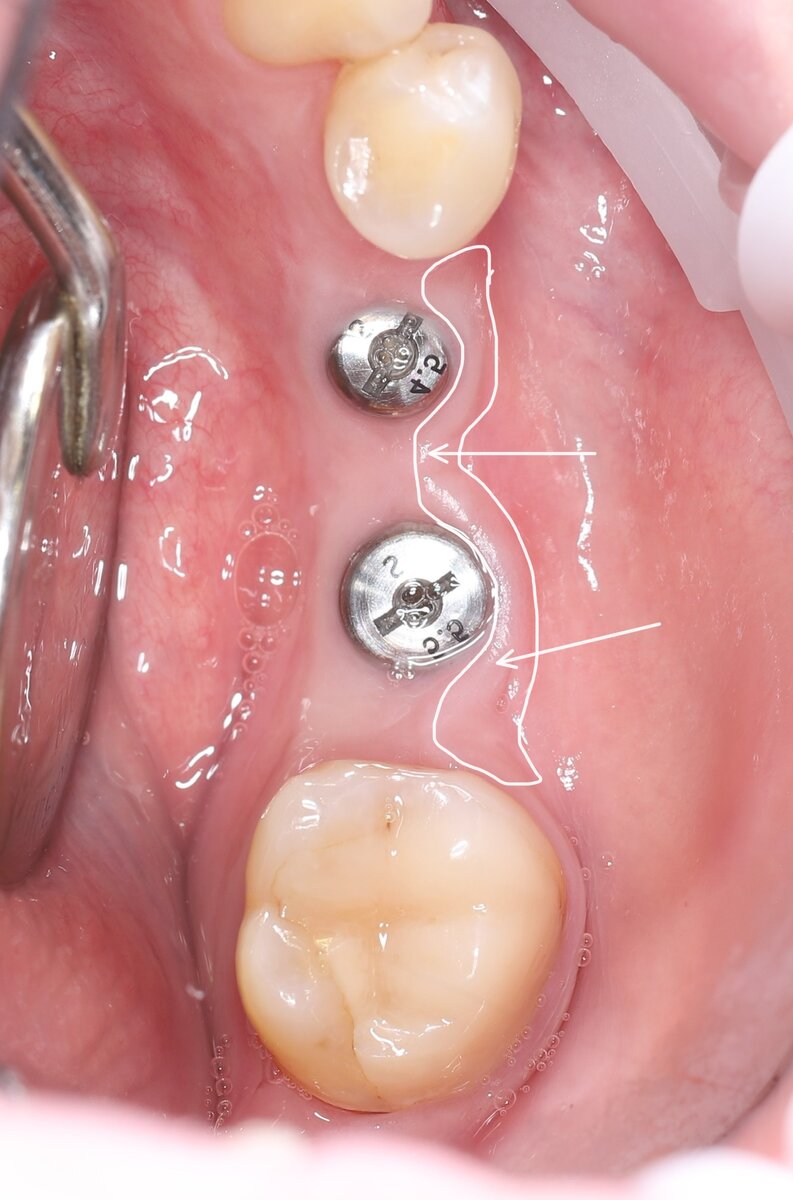

Посмотрите внимательно на это фото. Установлены имплантаты, в них закручены формирователи десны:

Здесь я установил 2 имплантата, но прикреплённой десны мало. ~ 1 мм с щёчной стороны:

И чтобы минимизировать в будущем риск заброса пищи в пространство между коронкой и имплантатом, нужно создать хороший объём неподвижной слизистой. Это будет своего рода барьер, не дающий проникать пищевым остаткам внутрь.

Для подобных десневых пластик мы зачастую используем донорские зоны. На фото схематично показал, где заимствуем донорские ткани для этих целей: